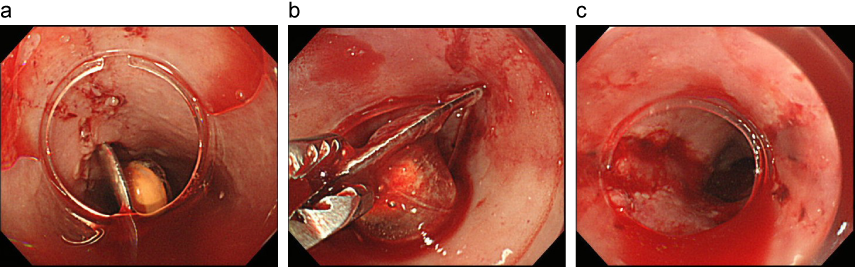

直腸異物(スプレー缶)例

a:腰椎麻酔下に経肛門的異物摘出術を施行した。

b:摘出されたスプレー缶

出典